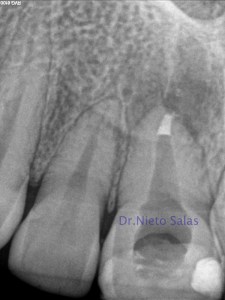

Después de realizarle un tratamiento de conductos a la pieza 2.1 que presentaba una periodontitis apical crónica que fístulizaba, el paciente nos llegó los 4 meses con una nueva presencia de la fístula.

Con un aparente, buen tratamiento de conductos, estaría indicado una cirugía endodontica frente a este fracaso endodóntico por vía ortógrada, ya que necesitaríamos la ayuda de una obturación retrógrada.

Evaluamos el caso con un CBCT

Una vez todo estudiado, preparamos el caso:

Pasados 4-5 días pasaríamos a retirar la sutura.

Después de un mes, le volvimos a citar: